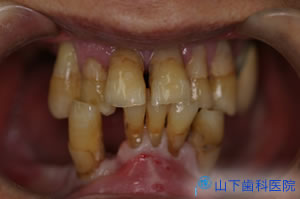

| 「入れ歯」では思うように噛めず、気持ち悪い。前歯で噛んでいるがぐらぐらしてきた。 残る歯もすっきりしない所が多々あり、今後に不安を抱えて来院されました。 |

| 初診時のレントゲン写真です。 | ![]() |

| 上下の奥歯が咬み合うことで決まる咬合が不安定で、下の前歯が上の前歯を突き上げています。 予知性がない右下、左上の4番目を抜歯して落ち着いた状態です。 |